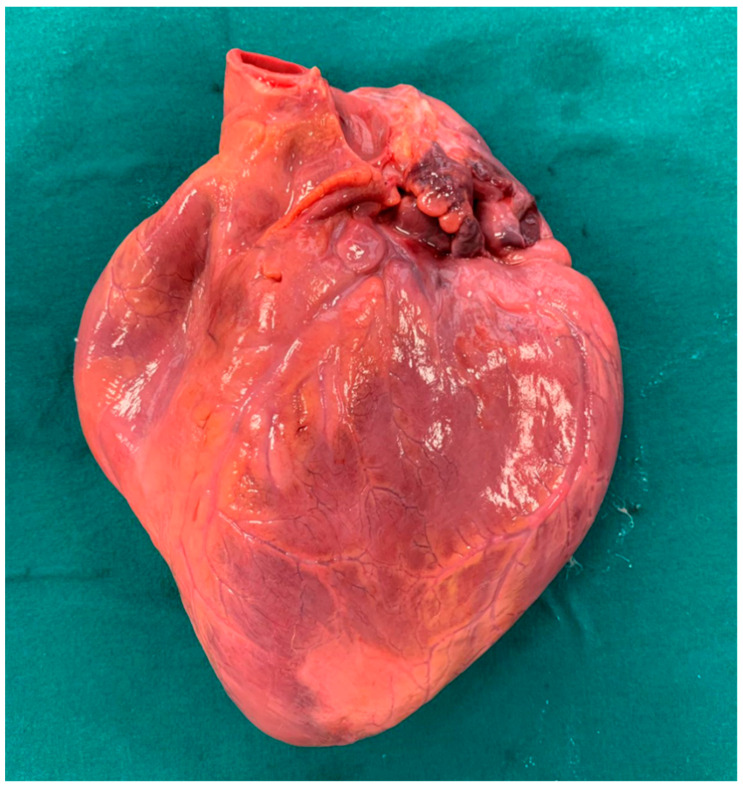

A 20-year-old young man (body mass index: 28) suddenly died in a public place. The friend who witnessed his death declared that he had recently smoked cannabis. All the witnesses said that the young man appeared in good health and that he suddenly collapsed (without any previous symptom). Basic life support maneuvers were promptly started, but when paramedics arrived, he was asystolic at ECG. The public prosecutor requested an autopsy to find the cause of the death. The victim played several competitive sports and had a syncope while playing football three years before. At external examination of the body no relevant sign was found. At the autopsy, performed five days after the death, the heart was isolated and fixated in toto in a 10% buffered formalin-based solution (Figure 1 and Figure 2). Both the lungs appeared swollen (weights: left—450 g, right—940 g), and multiorgan congestion was observed. Heart examination (weight: 530 g, longitudinal diameter: 11 cm, transverse diameter: 13 cm) presented no anomaly. Atria, valves, left ventricle (anterior wall thickness: 1.3 cm; lateral wall thickness: 1.4 cm; posterior wall thickness: 1.7 cm; interventricular septum thickness: 1.5 cm) and right ventricle (wall thickness: 0.5 cm) did not show any macroscopic relevant finding. Coronary circulation was right dominant. Left anterior descending coronary artery presented, at 2 cm from its beginning, a 0.3-cm-thick 5.5-cm-long myocardial bridging (Figure 3). Other coronary arteries were macroscopically normal. The conduction system was carefully analyzed, and serial sectioning targeted blocks of areas of interest [ref. 12,ref. 13]. Histopathological examination of the myocardium (Figure 4) found wavering of myocardial fibers, fibrosis and disarray in the left ventricle myocardial area above the MB (Figure 5); fibrosis in sino-atrial node area (Figure 6) and infiltration of fatty tissue (separated the myocardium) in the antero-lateral region of right ventricle free wall (Figure 7). The atrio-ventricular node presented no microscopic anomalies. No signs of myocarditis were found.